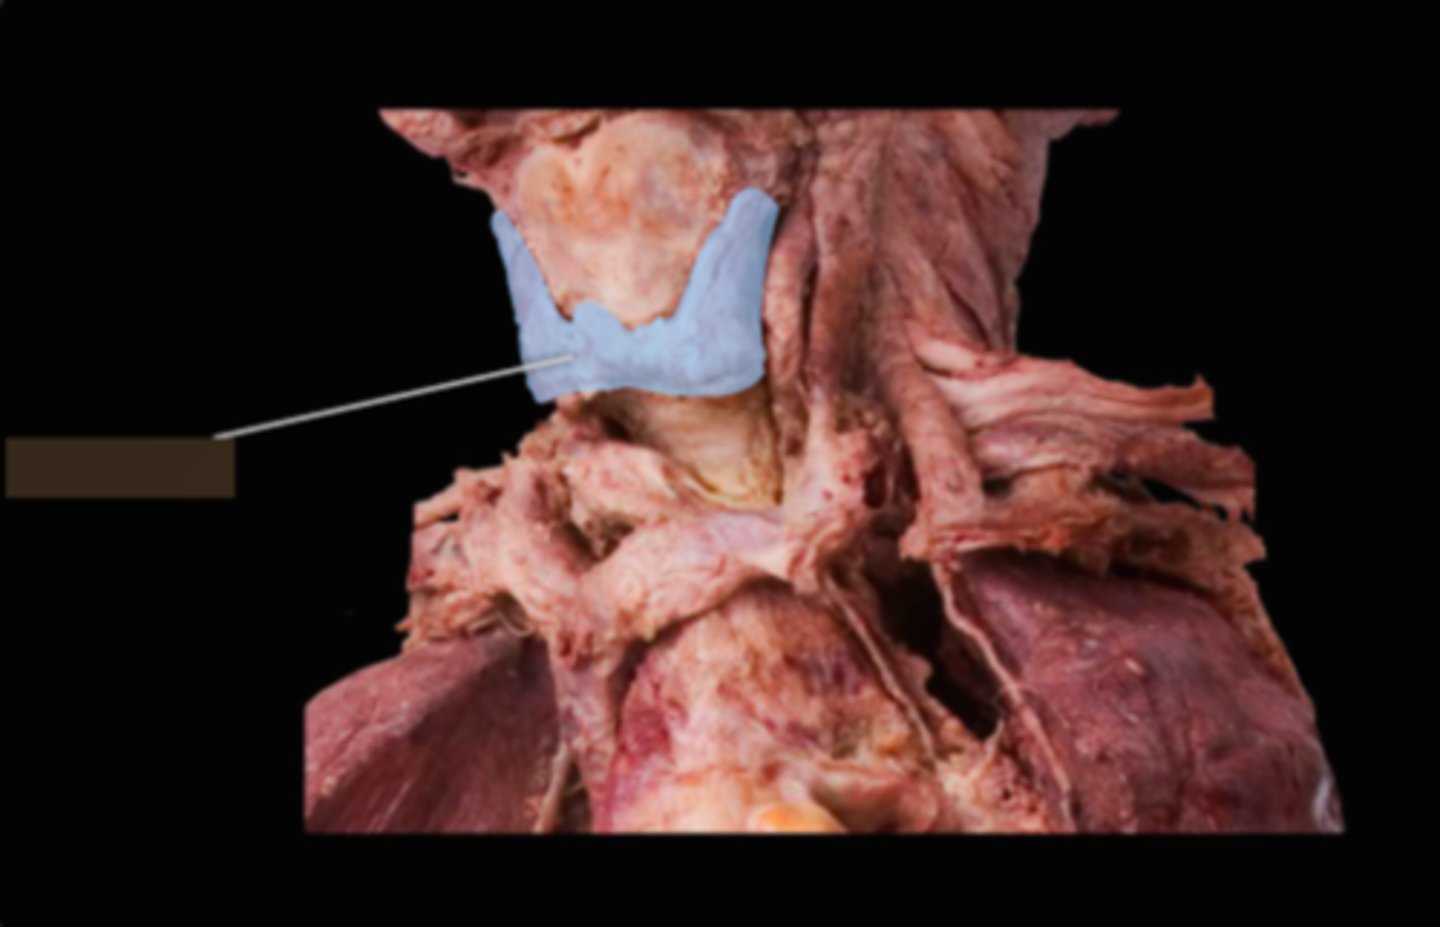

Thyroid Gland

Trachea